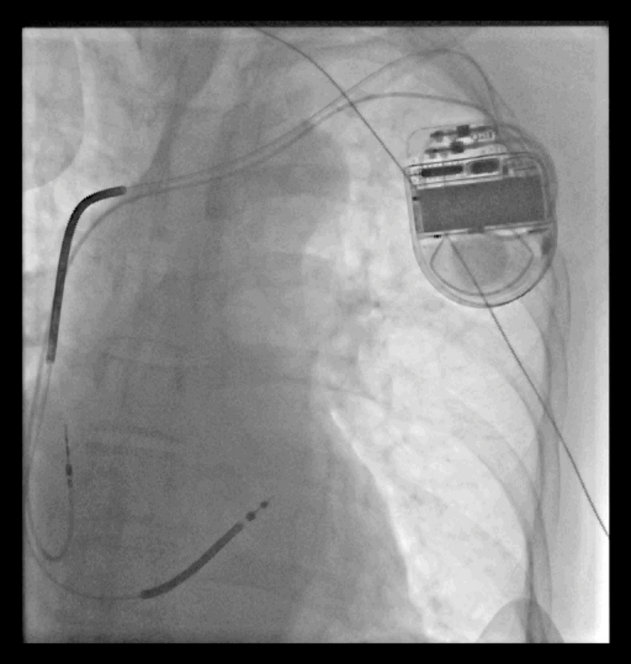

刘师傅的手术进行顺利,医生为刘师傅植入了美敦力ICD, 并在术后程控起搏器参数尽量减少心室起搏。这时候刘师傅的一颗悬着的心才稍微放宽了,本来害怕出院的担忧也逐渐被改变了。

一个月之后,刘师傅来门诊随访。自从安装了ICD,他感觉良好,感觉就像从未发过病一样。在随访问询中,发现刘师傅这一个月中有发生4次FVT事件,好在都被ICD成功捕获,ATP治疗成功,整个过程也就持续几秒钟,刘师傅根本没有察觉到。当医生告诉他这个事件的时候,刘师傅非常惊讶,原来自己以为的岁月静好,是因为有ICD在为他保驾护航,就像身边有一个机警的保镖时刻守护自己,顿时,之前的焦虑也几乎没有了,安全感十足。